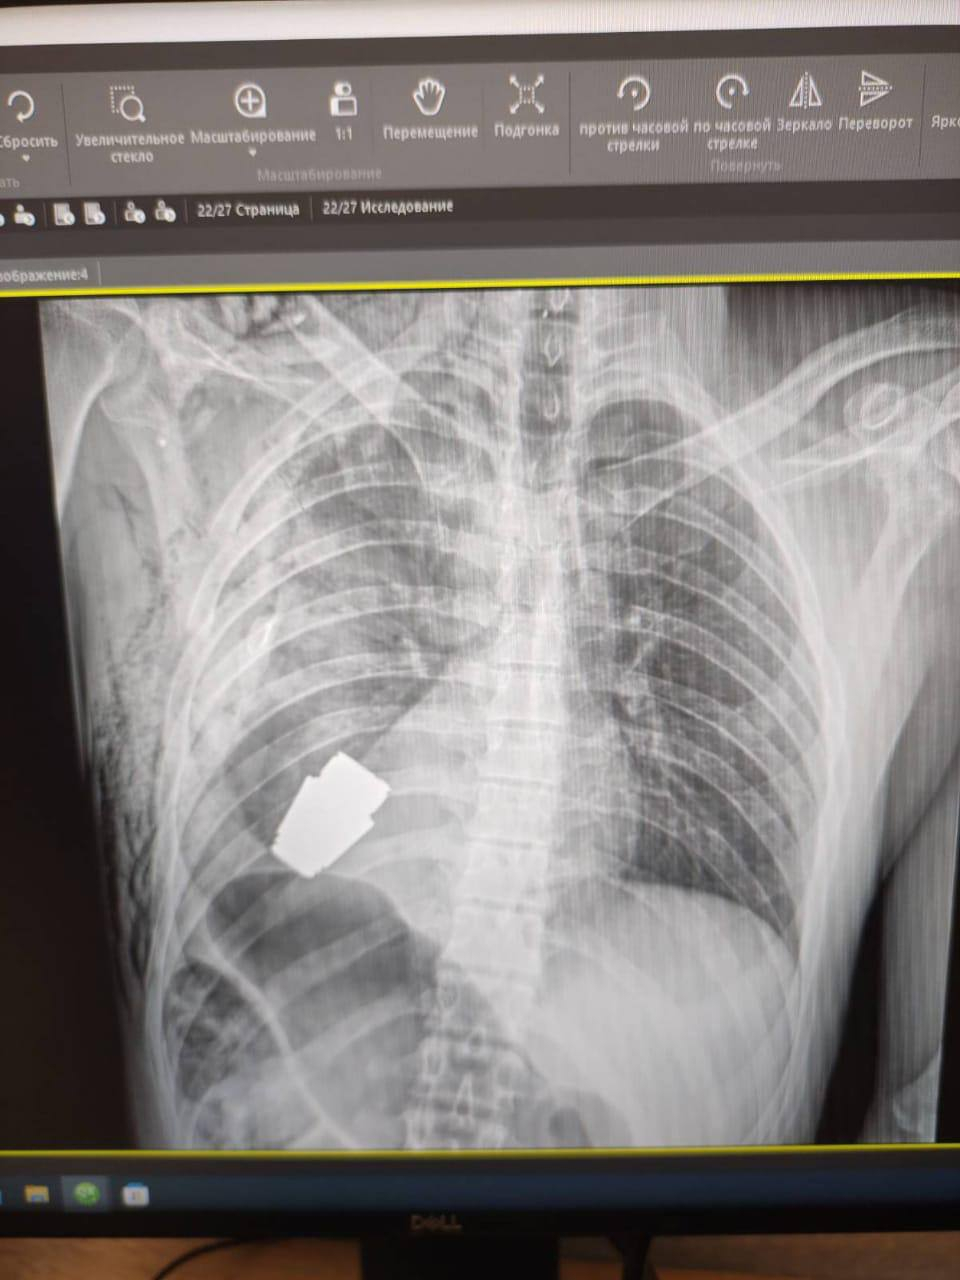

"Це шок. Приємний. Не кожне поранення в ділянці серця смертельне! Військові лікарі провели операцію з видалення гранати ВОГ, що не розірвалася, з тіла військовослужбовця. Вона була видалена в присутності двох саперів, які страхували безпеку медичного персоналу. Операція проводилася одним з найдосвідченіших хірургів ЗСУ - Андрієм Вербою без електрокоагуляції, оскільки граната могла здетонувати будь-якої миті. Оперативне втручання пройшло успішно, а пораненого військовослужбовця було відправлено на подальшу реабілітацію та відновлення", - розповіла Маляр.